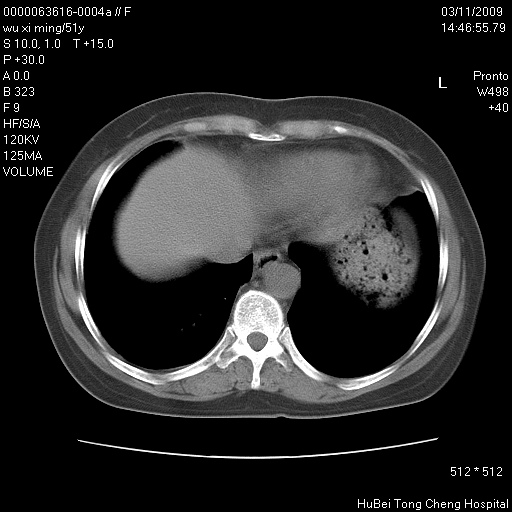

患者 女,51岁。因“胆囊炎,胆囊结石”,行常规术前胸部x线检查发现:右上肺结节病灶,建议行进一步检查。患者无咳嗽、咳痰及咯血等呼吸道症状,近期出现背部疼痛不适。

胸部ct轴位平扫(层厚10mm,螺距1.5,重建间隔10mm;部分层面:层厚3mm,螺距1.0,重建间隔3mm),图像如下:

右肺周围型肺癌伴肺内转移信胸椎转移

1、周围型肺癌。(毛刺正、血管束集征,分叶。)

集束征,胸膜牽拉征,毛刺,淺分葉高度提示ca.

右肺周围型肺癌伴肺内转移及胸椎转移。已无手术机会。